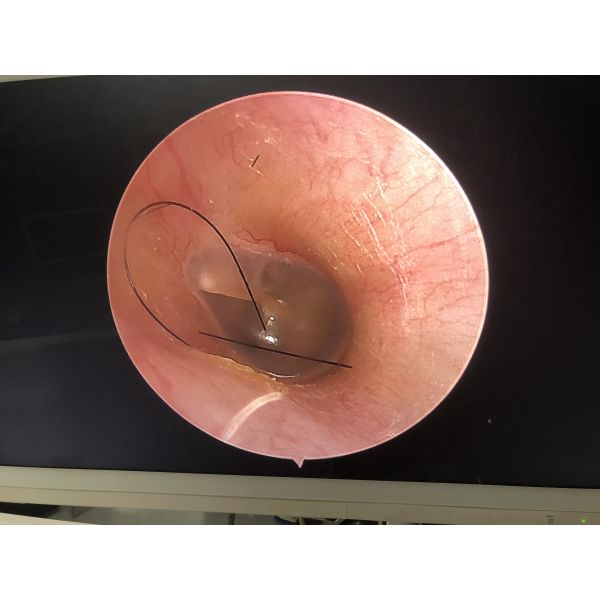

500 Unit/Units per Week Full HD Portable ENT Endoscopy System Medical Endoscope Camera

Medical Endoscope Camera

Application :

For Laparoscopy/gynecology/Urology/ENT surgery etc.